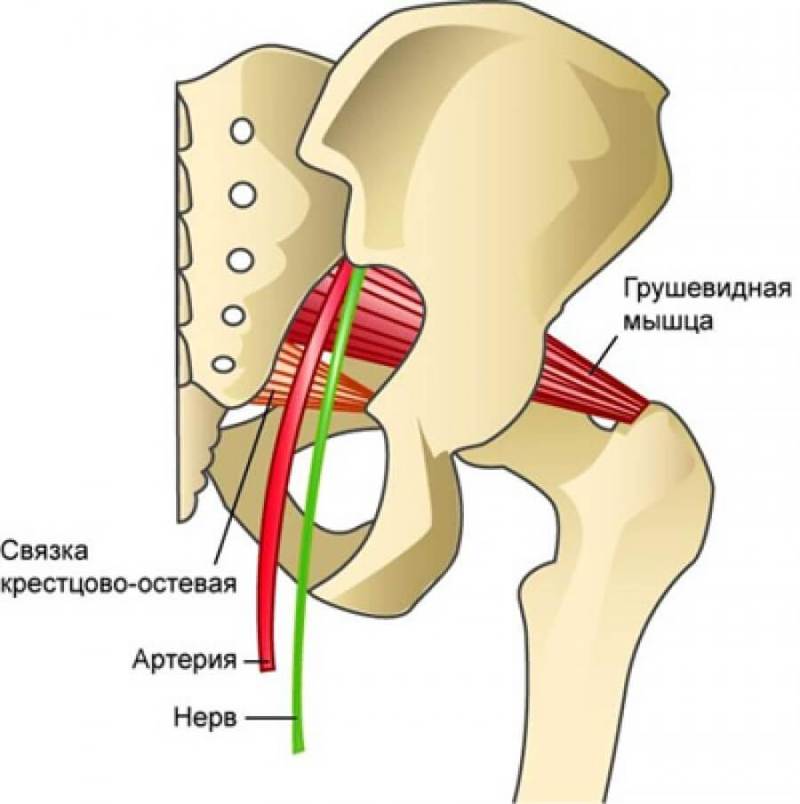

Анатомия мышц: Пириформис